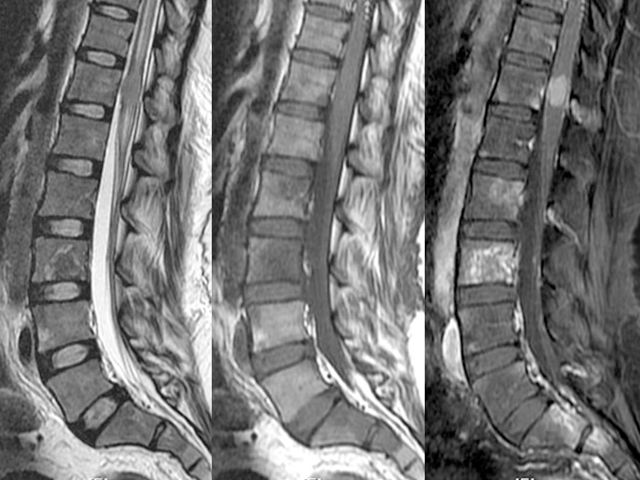

- МРТ или КТ. Диагностические мероприятия более информативны, чем рентгенография, позволяют выявить сужение позвоночного канала, деструкцию межпозвонковых дисков, тел позвонков. На полученных изображениях хорошо визуализируются кровоизлияния, неоплазии;